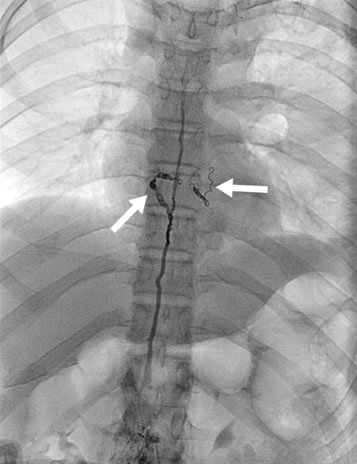

Embolization of leak (different patient) using coils